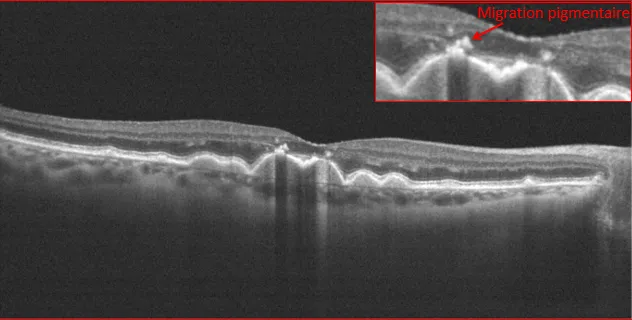

La CRSC est une affection chorio-rétinienne caractérisée par des soulèvements exsudatifs de la rétine.

Différentes incidences de coupe 2D par imagerie OCT de la région maculaire d'un patient présentant une bulle de DSR(Décollement séreux rétinien)

Les décollements séreux de la CRSC, qu’il ne faut pas confondre avec les décollements de rétine reghmatogènes, sont dus à l’apparition de points de fuites qui seraient liés à une hyperperméabilité, un épaississement et à une modification structurelle du réseau vasculaire profond sous la rétine qu ‘on appelle la choroïde . Cette entité rentre dans le spectre de maladie dénommé « Pachychoroïde ».

Troncs choroïdien dilatés dans le cadre d'une Pachychoroïde

Le diagnostic initial est établi grâce à l’imagerie tomographique appelée OCT (tomographie en cohérence optique).

Cet examen met en évidence le soulèvement rétinien localisé ainsi que l’épaississement de la choroïde sous-jacente. L’OCT permet également de détecter d’autres pathologies secondaires à la CRSC comme les néovaisseaux occultes sur pachychoroïde ou la vasculopathie polypoïdale choroïdienne. La détection précoce de ces affections permet souvent d’éviter des complications sévères avec parfois des pertes irréversibles de l’acuité visuelle.